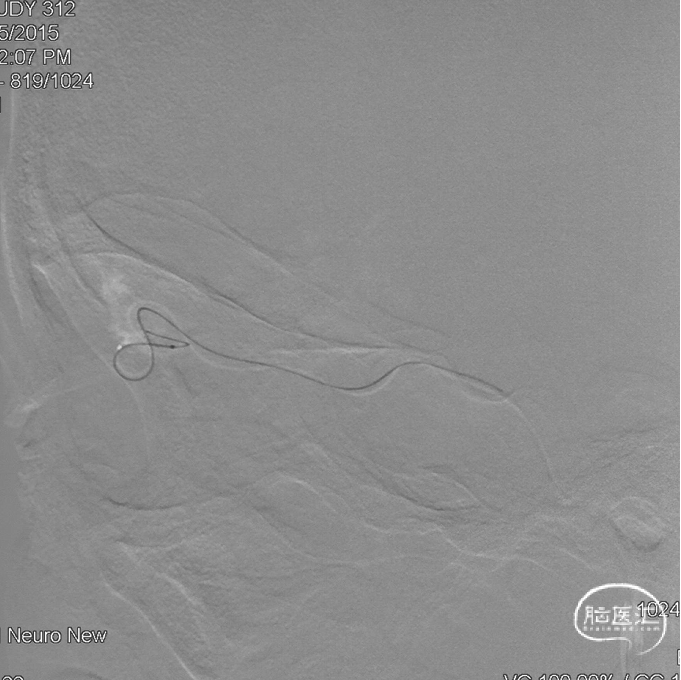

通过Marathon微导管注入Onyx 18,胶向瘘口弥散,并弥散至镰前动脉。

停顿后进一步注射Onyx18,此时胶向对侧筛前动脉弥散,直至闭塞瘘口和引流静脉起始端。